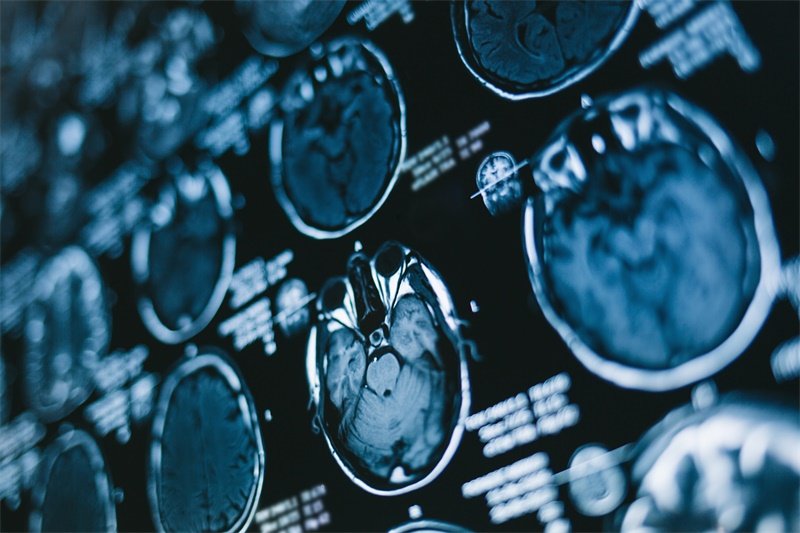

及时识别这些症状对于早期诊断至关重要。患者一旦出现上述症状,应及时就医,进行全面的影像学检查,如CT或MRI,明确蝶骨占位的性质及其对周围结构的影响。

影像学检查是诊断蝶骨占位的关键。常用的检查方法包括:

1. CT扫描:可以清晰显示蝶骨的结构及其周围组织的变化,帮助医生判断肿块的大小和范围。

2. MRI:对软组织表现更佳,能够评估肿块性质,尤其是是否侵及邻近重要神经和血管。

以上检查的准确性和清晰度能够为后续的治疗提供关键依据。